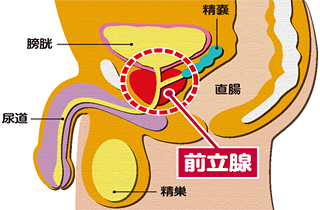

前立腺とは何ですか?

前立腺とは:膀胱の下で尿道を取り囲むようにあるクルミ大の臓器です。

はたらき:前立腺液を分泌し、精液の一部を作ります。